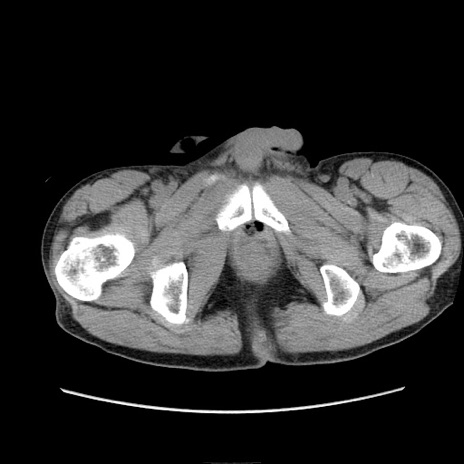

症例11(横断像)

【症例】 60歳代男性

【主訴】 下腹部痛

【現病歴】 本日夜中より下腹部痛の症状認め、受診。

【既往歴】 膀胱癌(膀胱全摘+尿管皮膚瘻術) 、胃癌術後

【身体所見】 BT 35.3℃、PR 58/min、BP 136/98mHg、腹部平坦、軟、腸蠕動音±、ストマ留置あり、左上腹部~正中部に圧痛あり、反跳痛なし。

【データ】WBC 5100、CRP0.01